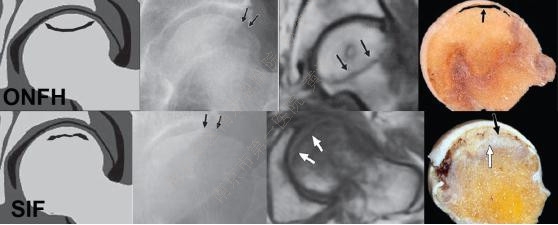

与ONFH类似,SIF典型的MR 表现同样为T1-W像中条带状的低信号并伴有骨髓水肿。

SIF的低信号条带多为不规则形、匍行、不连续、凸向关节面;ONFH的条带多较平滑、凹陷,并呈局限性。